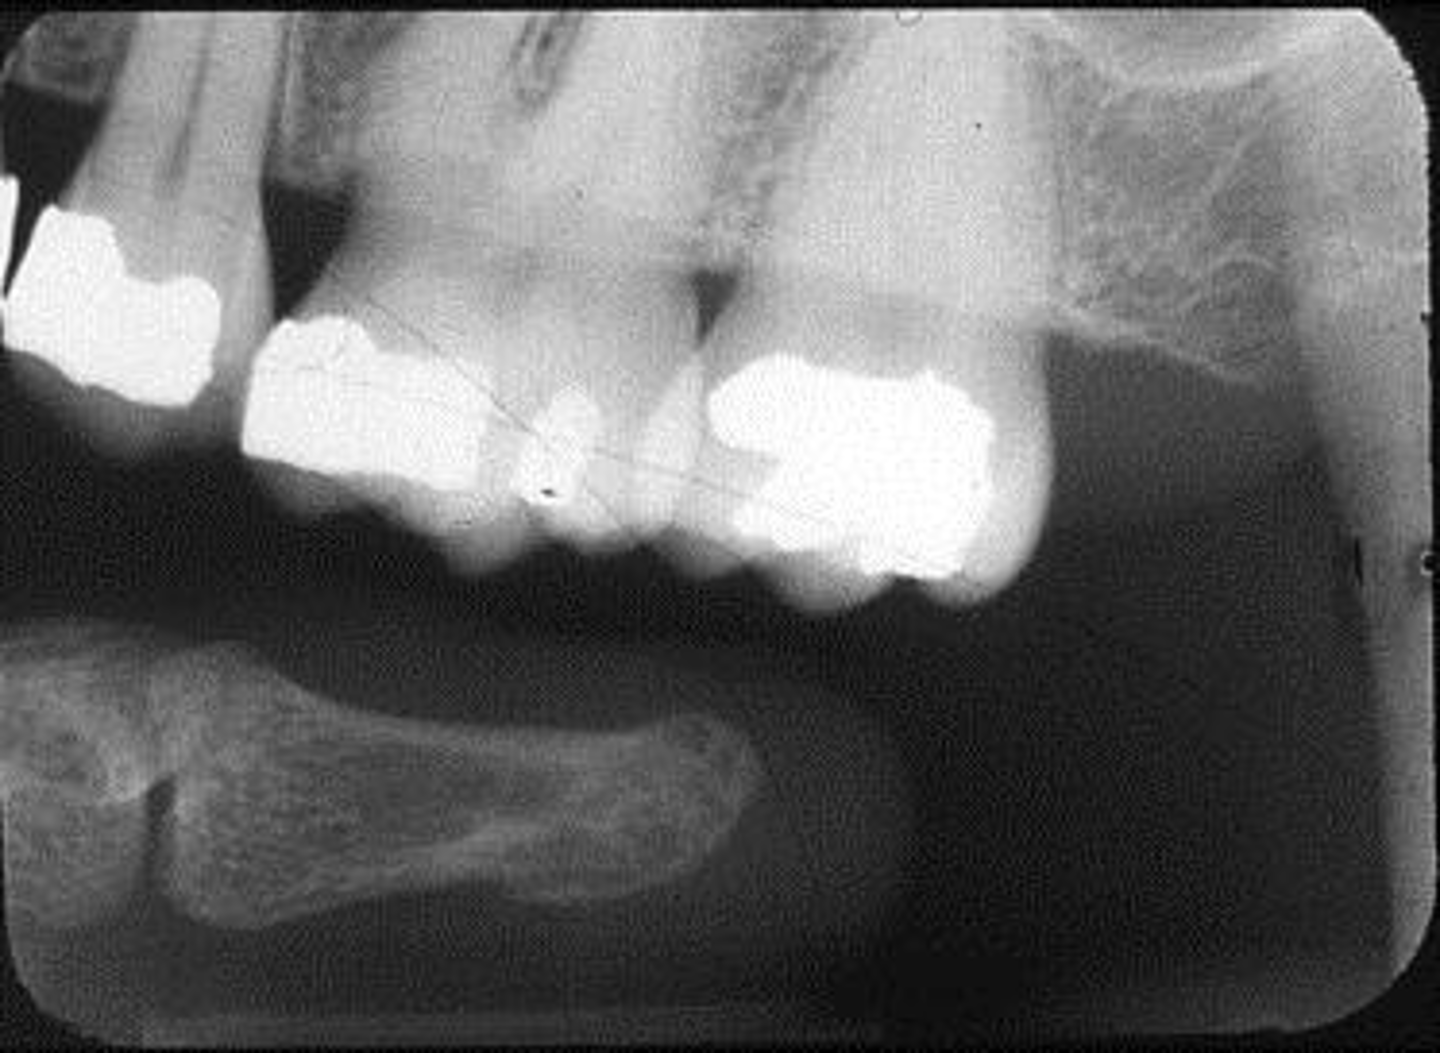

What is this error?

Wrong film direction, backwards, positive angulation, wrong film size, no open contacts